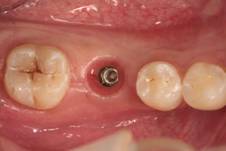

种植治疗是一种以植入骨组织内的下部结构(种植体)为基础来支持/固位上部修复体的缺失牙修复方式,是治疗牙齿缺失的一种较新的、成熟的临床技术。医生需要根据理想的缺失牙修复方案所要求的植体分布和三维方向、结合患者口腔局部和全身条件,设计制定合理的种植外科方案后,经手术方法将种植体植入组织内(通常是上下颌)、并获得骨组织牢固的固位支持,最后通过特殊的装置和方式连接支持上部的修复体。目前常用的种植体材料主要是钛、上部暴露于口腔内的修复体材料趋同于天然牙修复材料。

修复导向种植治疗方法的主要优点是主要依靠种植体的支持,恢复缺牙区的软硬组织形态、实现预期的功能与美学目标,这种方式更加符合口腔生物力学的要求,从而有利于获得更为长期的修复成功率。

(图片由修复科韩彦峰医生提供)